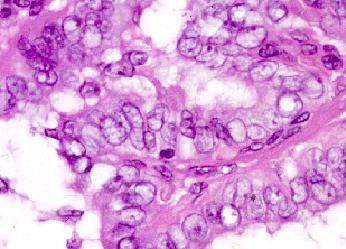

B. Papillary thyroid cancer.

Papillary thyroid cancer gives rise to characteristic ‘Orphan Annie Eye’ nuclear inclusions, which appear as blank spots.